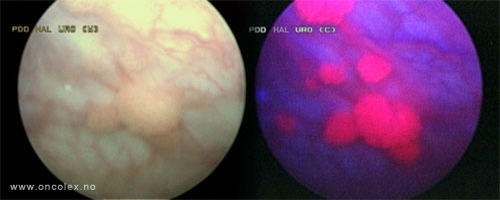

Bildeeksempler

Ved bruk av dette middelet i kombinasjon med et blått lys på cystoskopet, vil forandringer i urotelet vises i form av endret fargestruktur. Svulster vil da lyse rødt. Denne undersøkelsen betegnes fotodynamisk diagnostikk (PDD). Ved hjelp av denne metoden kan flere svulster oppdages på et tidlig tidspunkt sammenliknet med tradisjonell cystoskopi med hvitt lys alene.